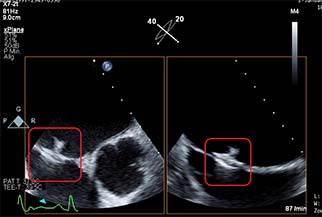

Within the first period, Vectorious successfully optimised the V-LAP system including the implant, the wearable device, and the data display software. The company also installed assembly facilities in-house to enable production of the implants and initiated production for use in the clinical trials. In January 2019, Vectorious initiated the VECTOR-HF first-in-human (FIH) clinical trial, and performed the successful first “in-human” implantation of the V-LAP monitoring device. Implantation of the device in this first “in-human” trial was completed in just six minutes. It was fixated within the patient’s interatrial septum of the heart using a standard minimally-invasive percutaneous procedure under fluoroscopy and echocardiographic guidance, with the application of local anaesthesia. By the end of the project, Vectorious successfully enrolled 13 patients in the trial across Germany, Italy, UK and Israel. The trial will continue after the project to ensure the collection of sufficient data for CE Marking.

Microcomputer in place